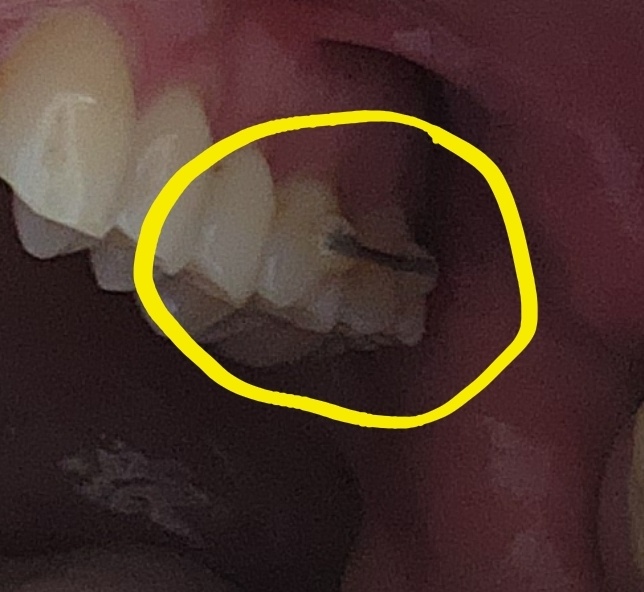

2021년 여름에 의사가 아마 금갔을꺼라고 해서, 그냥 있으나 없으나 한 이라 뽑았습니다.(역시나 금이가서 쪼개져 있었음)

- 7월 중순. 아래 어금니를 뽑았으므로 윗니가 점점 아래로 내려오는걸 방지하기 위한 줄을 옆에 이와 엮었습니다.(종합병원에서는 10만원 추가비용이 발생했습니다. 개인병원은 어떤지 모르겠네요.)

- 입 속에 뭔가를 하는데, 염증이 남았다면서 뭔가 긁어 냈고, 뼈이식이 들어갔고, 이내 다 심었답니다.